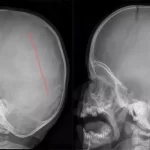

شکستگی جمجمه: نشانهها، عوارض، تشخیص و درمان

پیچیدهترین ساختار بشر، جمجمه است که به عنوان کلاه خود واقعی مغز عمل میکند. وقتی این خط اول دفاعی مورد حمله قرار گیرد، عواقبی جدی به دنبال خواهد داشت. شکستگی جمجمه، یکی از شایعترین انواع آسیبهای ناشی از ضربه است که میتواند زندگی فرد را […]